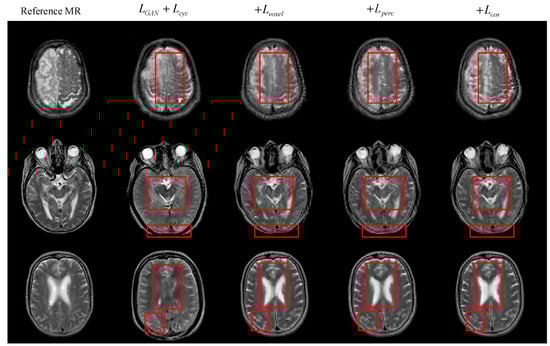

4.2. Comparison of Results under Different Objective Optimization Functions

| MAE ↓ | RMSE ↓ | PSNR ↑ | SSIM ↑ | PCC ↑ | |

|---|---|---|---|---|---|

| LGAN | 19.054 | 36.343 | 65.157 | 0.52 | 0.761 |

| +Lvoxel | 13.163 | 25.844 | 68.423 | 0.647 | 0.869 |

| +Lperc | 13.141 | 25.636 | 68.476 | 0.645 | 0.87 |

| +Lcos | 12.981 | 25.532 | 68.519 | 0.652 | 0.872 |